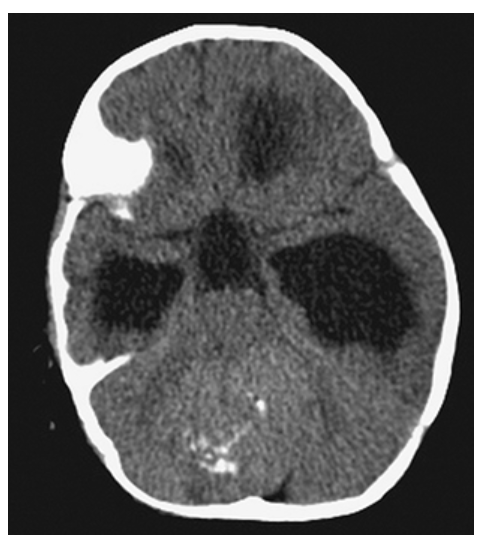

Dandy-Walker Syndrome. Axial NECT shows a large posterior fossa with a CSF density cyst, hypoplastic cerebellar hemispheres, and absence of the vermis.